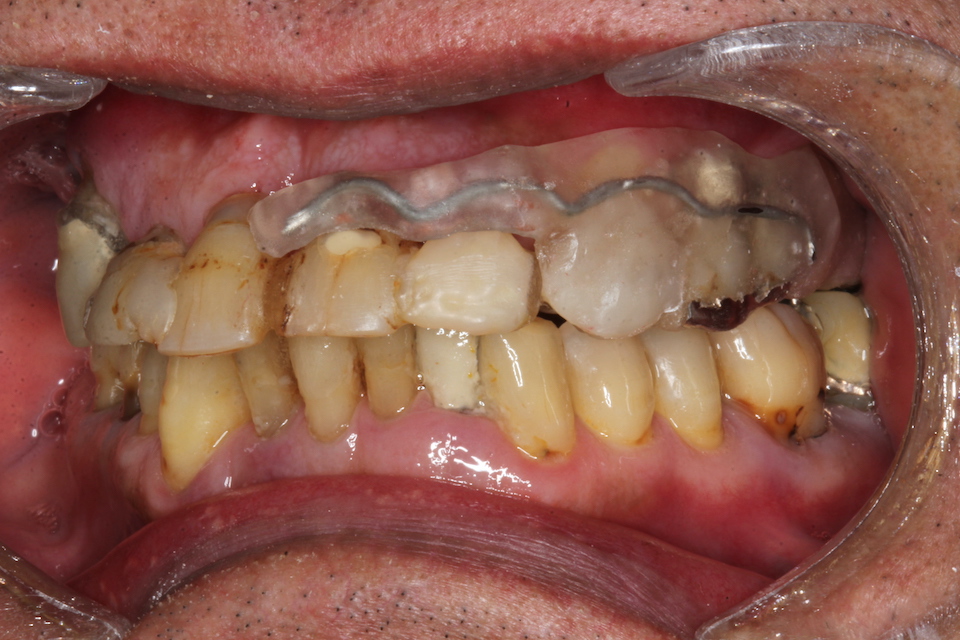

パッチン義歯2.1(削らないブリッジ) 2025.11.04

半口腔内製作義歯1.0 2025.06.24

半口腔内製作義歯0.6 2025.06.17